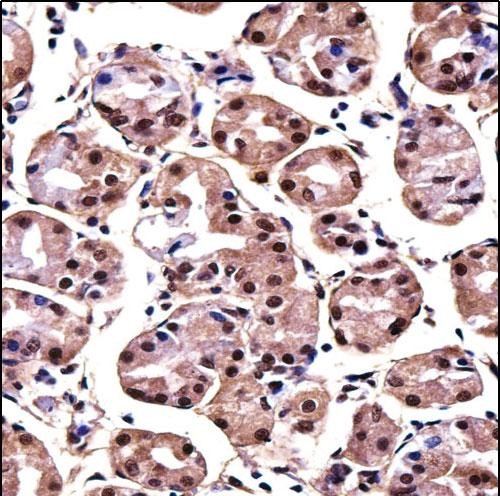

| IHC | 1/100-1/500 | Human,Mouse,Rat |

| Immunogen | This MAGOH antibody is generated from rabbits immunized with a KLH conjugated synthetic peptide between 46-74 amino acids from the Central region of human MAGOH. |